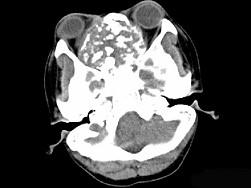

问题 男性,28岁,因鼻塞、头痛1年余,鼻窦CT扫描如图所示,请选择正确的描述与结论 ( )

选项 A、考虑鼻窦骨瘤 B、考虑为鼻窦软骨瘤 C、肿块内密度不均,有较多致密钙化影 D、窦壁及颅底骨质破坏 E、双侧上颌窦、筛窦、鼻腔及蝶窦内见软组织肿块影

答案 BCDE